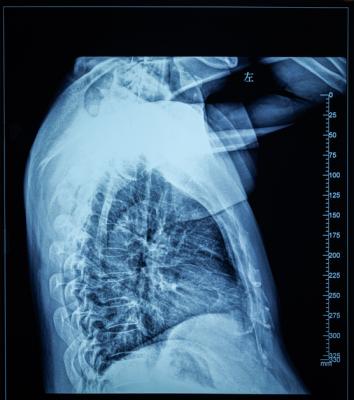

April 30, 2021 — For many patients with localized lung cancer (non-small-cell lung carcinoma and small cell lung carcinoma), high-dose radiation with concurrent chemotherapy is a potential cure. Yet this treatment can cause severe, acute inflammation of the esophagus (esophagitis) in about one in five patients, requiring hospitalization and placement of a feeding tube.

A team of radiation oncologists at Mass General Cancer Center demonstrate in an early clinical trial that the radiation beam can be carefully "sculpted" to deliver the majority of a radiation dose directly to the tumor while effectively sparing tissues in the side of the esophagus away from the affected lung (the contralateral esophagus), thereby limiting inflammation and preserving swallowing function.

The technique involves imaging the esophagus and then shaping a high-dose radiation beam so that the maximal amount of radiation energy is delivered to the tumor, with a steep dropoff in energy across the esophagus, thereby sparing as much as possible the normal tissues and function in the side of the esophagus farthest away from the treatment site.